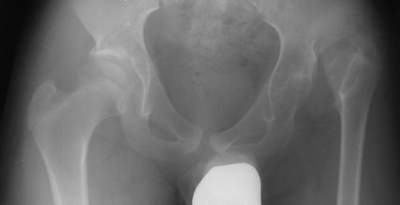

"Поздний" (14 лет) врожденный вывих (подвздошный) бедра |

Dear collegues,Мальчик, 14 лет. Из Узбекистана...Никакой документации на данный момент нет, но со слов выяснилась приблизительно следующая картина... Патологию диагностировали в 2 года...якобы она была двусторонней (скорее всего дисплазия справа и вывих слева),лечили то ли функционально то ли закрытым вправлением под наркозом...как бы то ни было около года гипсовался в различных позах по-Лоренцу...Потом вроде бы повязка сломалсь (слева) и родителям сообщили о рецидиве вывиха...С тех пор (с 3 лет) никак не лечился...С возрастом стало возникать укорочение левой н. конечности, что особенно то и не беспокоило как выяснилось...2 года назад (12 лет) появились боли в левом тазобедренном суставе (на стороневыцвиха)...Вот это то (боли) и являются главной причиной обращения в данное время (14 лет).Укорочение левой н. конечности на 5 см не воспринимается как главная проблема...Снимки в приложении.Что делать?